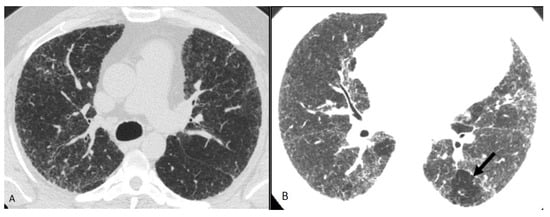

- Johannson, K.A.; Elicker, B.M.; Vittinghoff, E.; Assayag, D.; Boer, K.; Golden, J.A.; Jones, K.D.; King, T.E., Jr.; Koth, L.L.; Lee, J.S. A diagnostic model for chronic hypersensitivity pneumonitis. Thorax 2016, 71, 951–954. [Google Scholar] [CrossRef]

- Silva, C.I.S.; Muller, N.L.; Hansell, D.M.; Lee, K.S.; Nicholson, A.G.; Wells, A.U. Nonspecific interstitial pneumonia and idiopathic pulmonary fibrosis: Changes in pattern and distribution of disease over time. Radiology 2008, 247, 251–259. [Google Scholar] [CrossRef]

| At least one finding indicative of pulmonary fibrosis | Variant pattern of fibrosis | |

| Coarse reticulations with distortion | UIP pattern of fibrosis | |

| Traction bronchiectasis | Extensive GGO and superimposed subtle fibrosis | |

| Honeycombing (not dominant) | ||